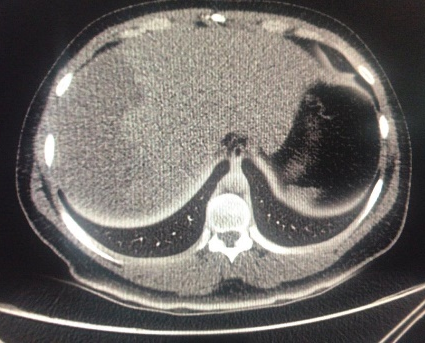

ERCP was performed successfully over 0.035-inch diameter guidewire, a Haraldsson type 3 duodenal papilla;3 Cholangiography showed a fill defect of 8mm, with a no bleeding, complete sphincterotomy, the common bile duct stone was extracted with balloon, without complication. Patient was followed for 6hours, and previous discharge, pain appeared at right upper quadrant. Colicky pain, diaphoresis, nausea and vomiting. We made new laboratory test, showing, and a drop of hemoglobine from 15g/dl previously to 10g/dl creating us the idea about patient was bleeding, maybe from the sphincterotomy, just giving no surgical management until then. Urgent computed tomography (CT) scan exhibited 13x11 cm subcapsular hepatic hematoma on the surface of the right hepatic lobe (Figures 1-4). He was treated with conservatory management with Tomographic control every 10days in 2 episodes, and every 2months, with hematoma regression until the month 6th.

Figure 3 48 Hrs CT control. Density changes.